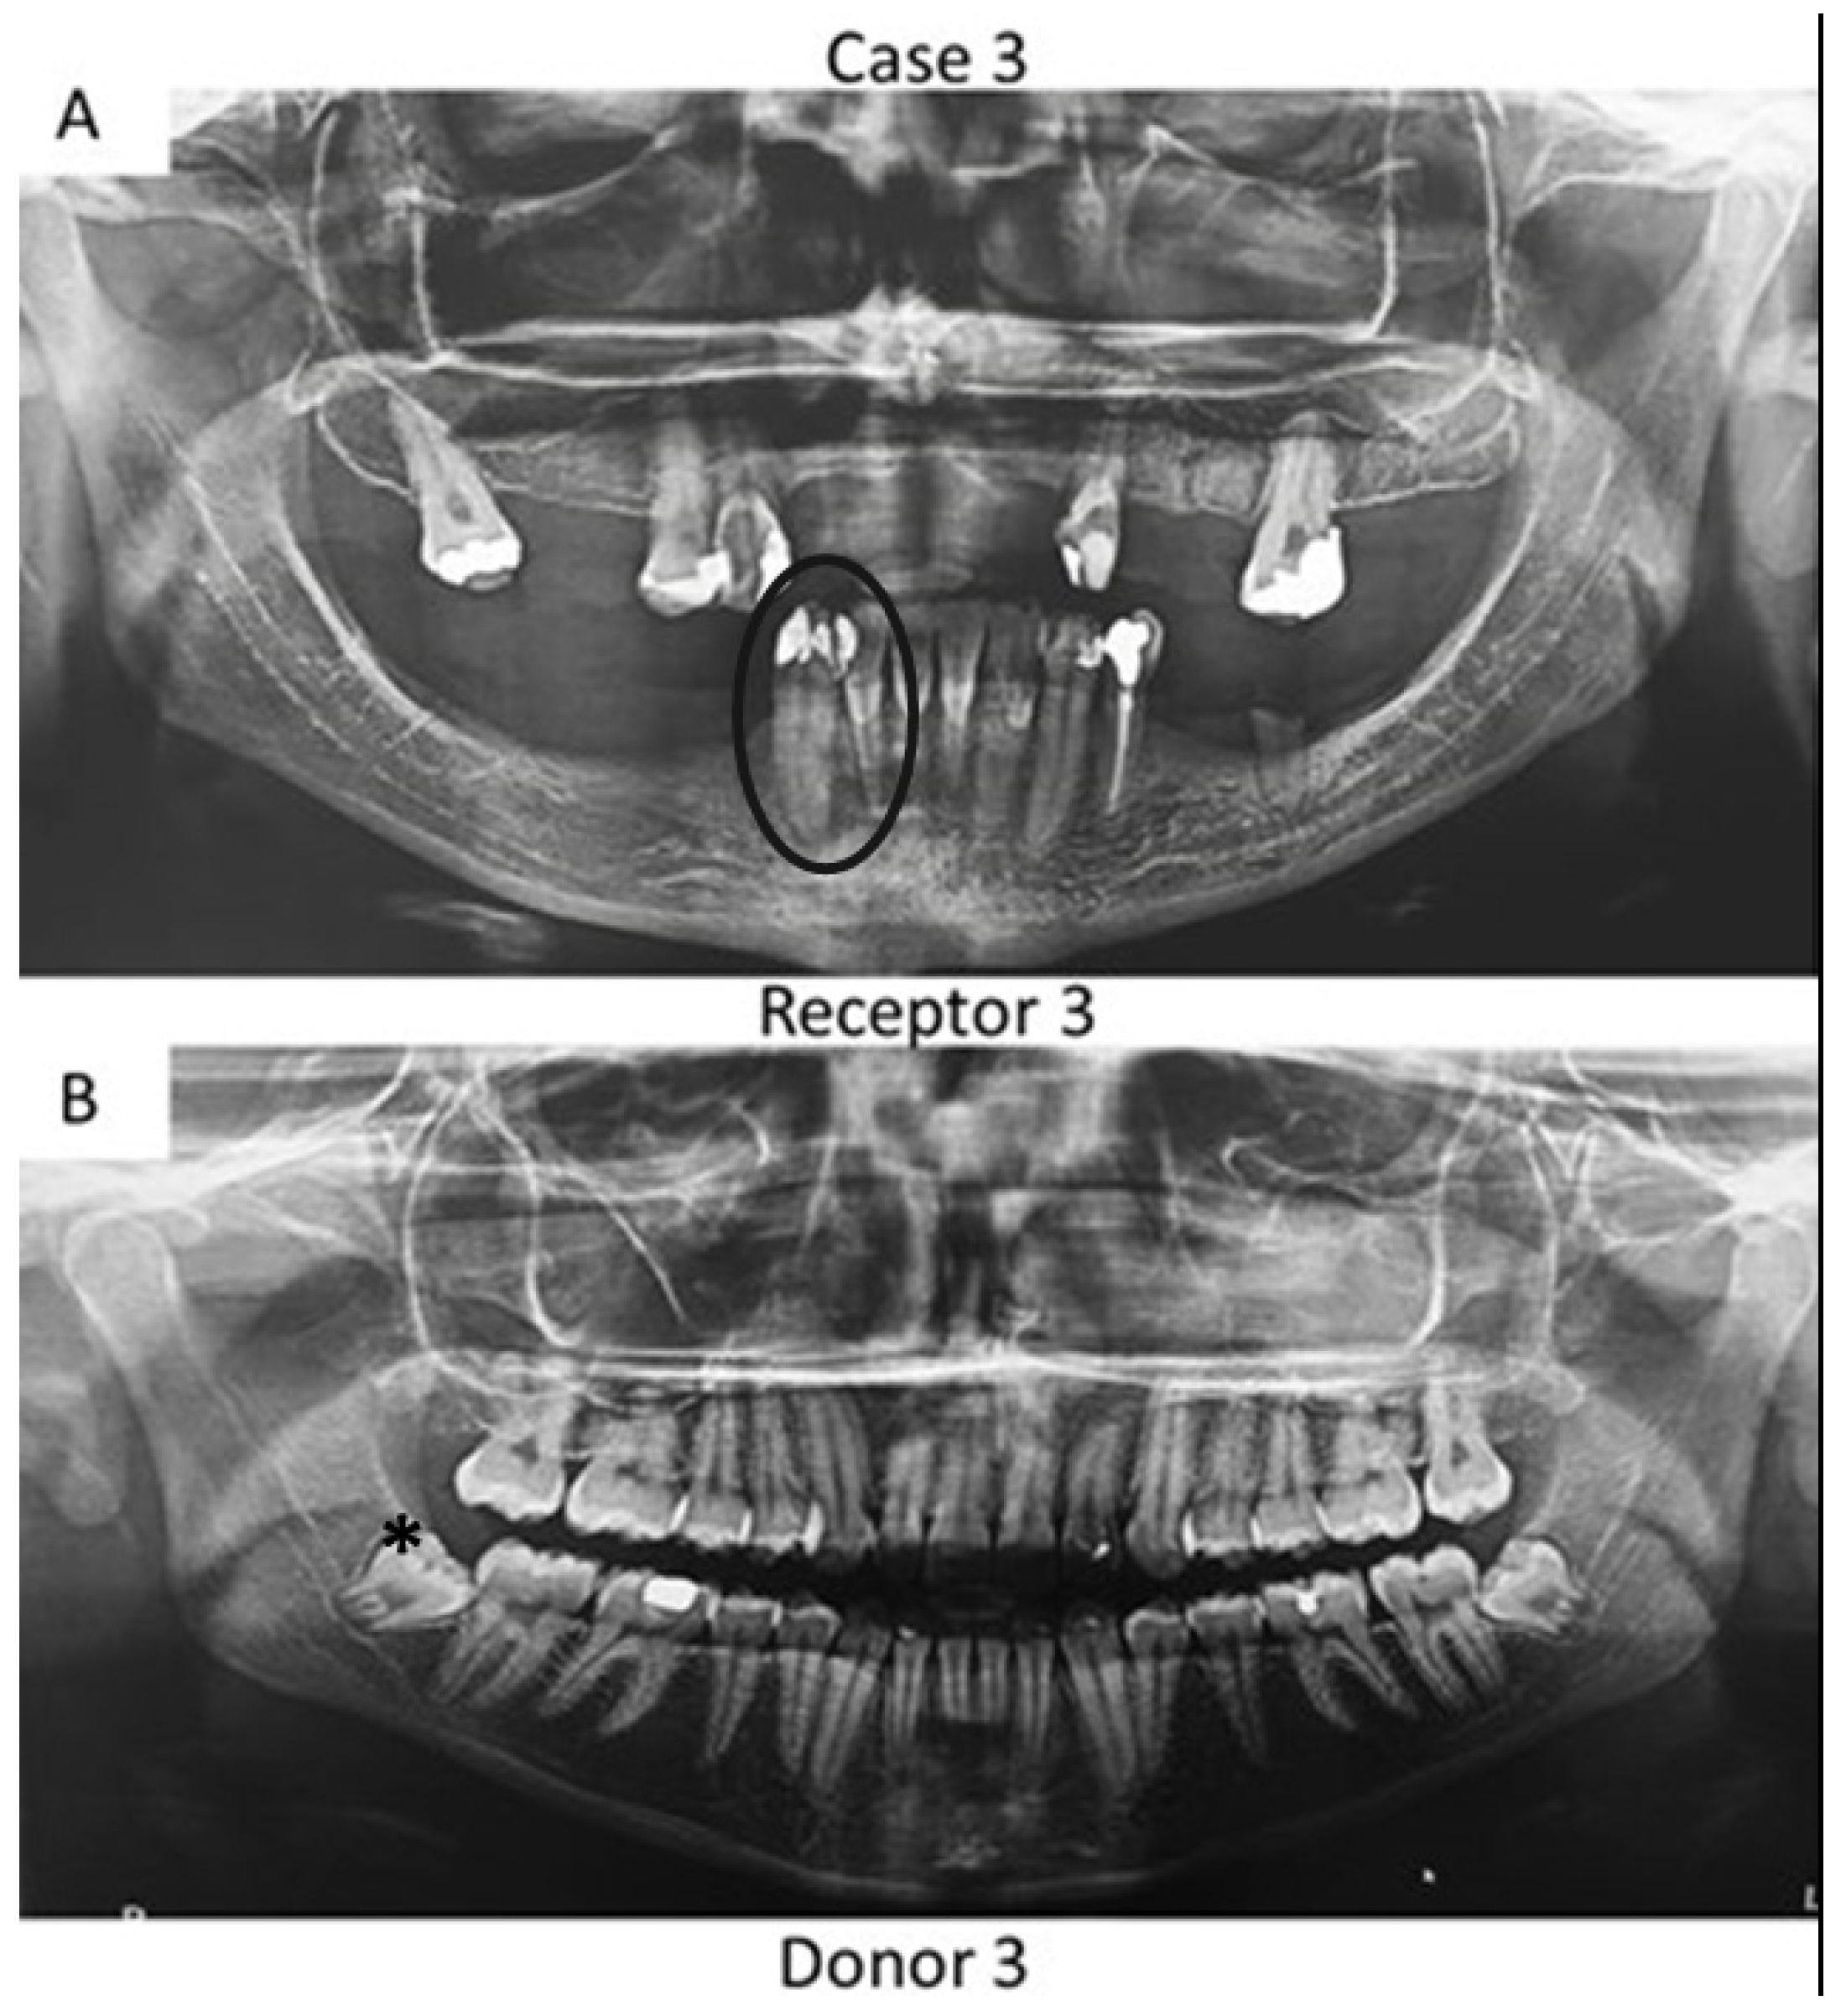

First, panoramic radiography was performed on all patients in the three cases (Figure 1, Figure 2 and Figure 3), as well as computed tomography (CT) scanning with a 0.25 mm voxel size in order to confirm the periapical status of each tooth requiring endodontic treatment. The extraction of teeth from the patients’ children was performed without tooth sectioning and with extreme caution in order to avoid damaging the tooth and the apical structures. The extraction was carried out with local anesthesia using 1.8 mL of 2% lidocaine (1:80,000 epinephrine) through a nerve block technique. The extracted teeth were stored in a sterilized saline solution. At the same time and in the same dental office, the single-root teeth requiring root canal treatment were also anesthetized as aforementioned, isolated with a rubber dam, and pulp chamber access was executed with diamond burs with a high-speed handpiece under continuous and copious water irrigation. The canal instrumentation was performed using rotary files (Wave One Gold, Dentsply, Rio de Janeiro, Brazil) in combination with irrigation using a tri-antibiotic solution (ciprofloxacin, minocycline, and metronidazole at 500 μg/mL each) [14,15]. Prior to the rotary files, one #10 manual K-file (Dentsply) was used to perform the patency. No apical bleeding was performed because it was a different protocol than the revascularization strategy [15,16].

Figure 3. Panoramic radiographs of initial visit of the further two patients. Black circle indicates the teeth requiring root canal treatment (receptor teeth: lateral incisor and canine) in the mother whilst the asterisk highlights the third molar from the daughter demanding extraction (pulp donator tooth). The pulp from the donator tooth was sliced to obtain a mesial portion, which was transplanted to the lateral incisor of the mother; meanwhile, the distal part of the pulp was inserted into the mother’s canine.